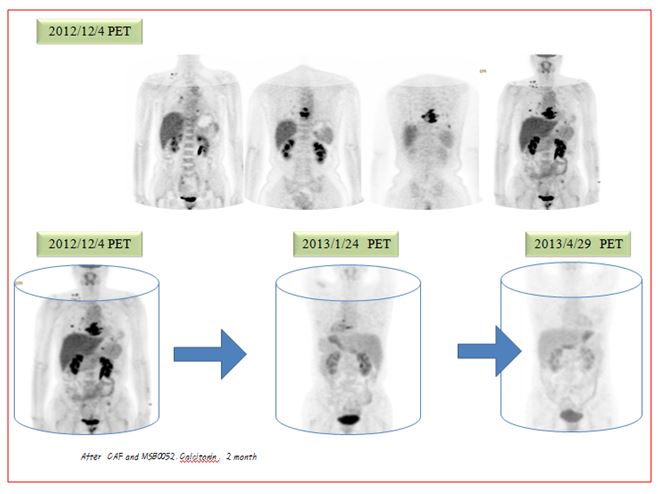

6-4

그림1 좌측 사진은 bonescan으로 별 다른 이상이 보이지 않는다. 우측 사진은 내원 초기에 찍은 PET로밝은 음영이 척추에 보이는 부분이 종양이 전이된 부분이다. 폐에는작은 nodule이 수많이 점점으로 있는데 이 사진에서는 보이지 않는다. 이 환자는 herceptin 수용체가 있는 경우여서 초기에 taxol과 herceptin을 생각하였으나 나의 권고에 의해서 taxol은 사용치 않고  CAF 이후에 herceptin을 사용하기로 하고 협진하는 병원에 의뢰하여서 이 방법을 한방치료와 같이 시행하였다. 내원 초기에 CT에서  소견서에 따르면 multiple small nodules both lungs hematogeneous metastasis likely –수많은 작은 종양들이 양쪽 폐에 보인다. 혈행성전이로 판단된다. 이밖에도 척추에도 전이가 되어 있었고 골반부위에도 전이가 되었고 임파절도 여러 군데 전이가 보였다. 그리고  4개월 뒤에 결과는 다음과 같이 좋아졌다.

6-5

그림2  위의 사진은 역시 PET 사진으로 척추 아래 왼쪽으로 간이 보이고 그 아래에 검은 음영은 조영제가 신장으로 내려가는 부분으로 정상 부위이다. 여기를 제외한 제일 우측 사진에서 보이는 오른쪽 어깨의 점이 목의 림프절 전이이고 이밖에도 좌측 골반 부위에도 자세히 보면 검은 점이 나타나는데 이 부분 역시 종양이 전이된 부분이다. 중간에도 오른쪽으로 간 위에 점이 보이는 부분이 7th갈비뼈에 전이가 된부분이다.  2012년 12월 4일에 비해서 치료초기 2013년 1월 24일 아래의 중간 사진을 보면 음영이 많이소실이 되어 있고 치료 5개월 뒤인 제일 우측 사진에서는 종양의 흔적이 잘 안 보인다. 환자는 한양방 통합치료 한 달 뒤에 종양이 확연히 줄어들기 시작하였다. 두 달 뒤 PET에서 흉추 7번과 왼쪽 갈비뼈 7번의 뒤편 그리고 흉추 6번 등에 아직은 조영증가 소견을 보이지만 2012년 외부 필름에서 보이던 오른쪽 경부의 림프절과 양쪽 폐의 종양과 왼쪽 골반은 호전되어서 보이지 않게 되었고 이후에도 더욱 종양이 줄어들었다